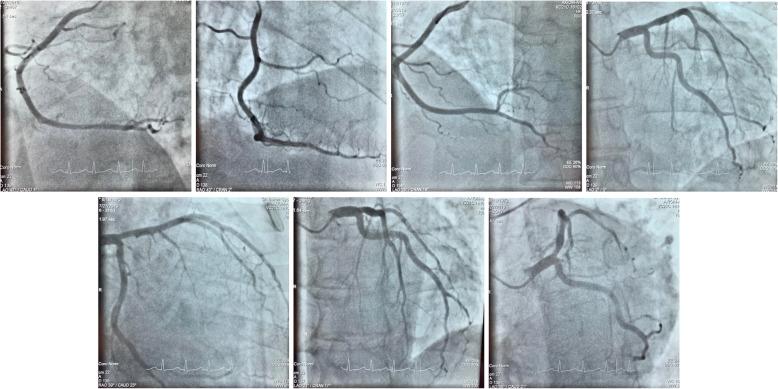

Forty-eight-year-old diffuse large B cell lymphoma patient was admitted to our emergency department with chest pain, effort dyspnea, and fever. The patient had normal blood pressure, blood oxygen saturation, sinus tachycardia, fever, crackles over the left lower lobe, novum incomplete right bundle branch block with Q waves and minor ST alterations, elevated C-reactive protein, high-sensitivity troponin-T, and d-dimer levels. Chest X-ray revealed consolidation on the left side and enlarged heart. Bed side transthoracic echocardiography showed inferior akinesis with pericardial fluid. Coronary angiography showed no occlusion or significant stenosis. Chest computed tomography demonstrated the progression of his lymphoma in the myocardium. He was admitted to the Department of Hematology for immediate chemotherapy and he reached complete metabolic remission, followed by allogeneic hematopoietic stem cell transplantation. Unfortunately, about 9 months later, he developed bone marrow deficiency consequently severe sepsis, septic shock, and multiple organ failure what he did not survive.

Our case demonstrates a very rare manifestation of a heart metastasis. ACS is an unusual symptom of cardiac tumors. But our patient's intramyocardial lymphoma in the right atrium and ventricle externally compressed the right coronary artery and damaged the heart tissue, causing the patient's symptoms which imitated ACS. Fortunately, the quick diagnostics and immediate aggressive chemotherapy provided the patient's remission and suitability to further treatment.

一名48岁的弥漫性大B细胞淋巴瘤患者因胸痛、劳力性呼吸困难和发热入住我院急诊科。患者血压正常、血氧饱和度正常、窦性心动过速、发热、左下叶可闻及湿啰音、新出现的不完全性右束支传导阻滞伴Q波和轻微ST段改变、C反应蛋白升高、高敏肌钙蛋白T及D - 二聚体水平升高。胸部X线显示左侧实变及心脏增大。床旁经胸超声心动图显示下壁运动减弱伴心包积液。冠状动脉造影显示无闭塞或明显狭窄。胸部计算机断层扫描显示其淋巴瘤在心肌内进展。他被收入血液科立即进行化疗,并达到完全代谢缓解,随后接受异基因造血干细胞移植。不幸的是,约9个月后,他出现骨髓抑制,继而发生严重脓毒症、感染性休克和多器官功能衰竭,最终死亡。

我们的病例展示了一种非常罕见的心脏转移表现。ACS是心脏肿瘤的一种不寻常症状。但我们患者右心房和心室的心肌内淋巴瘤向外压迫右冠状动脉并损伤心脏组织,导致患者出现类似ACS的症状。幸运的是,快速诊断和立即积极化疗使患者缓解并适合进一步治疗。